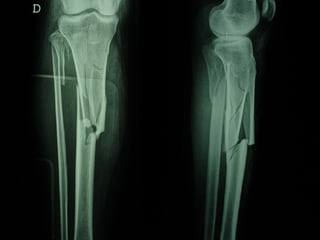

Dal Gennaio 2000 al Febbraio 2006 abbiamo trattato 167 fratture chiuse  con placca percutanea  in 164 pazienti :  27 lesioni diafisarie di gamba, 12 piloni tibiali ,  11 fratture prossimali di tibia, 36 fratture sovracondiloidee di femore, 17 fratture diafisarie di femore, 43 fratture metaepifisarie prossimali di omero, 21 diafisarie d’omero.  156 guarigioni 8 fallimenti

Dal Giugno 2002 al Dicembre 2004 abbiamo trattato 5 fratture esposte: 3 di tibia e 2 di ulna 5 guarigioni

I buoni risultati ottenuti dipendono da 5 punti fondamentali:   una accurata riduzione percutanea della frattura  precise vie di accesso  l’utilizzo della placca che consenta il più lungo braccio di leva possibile il pretensionamento della placca  una sintesi con un ridotto numero di viti